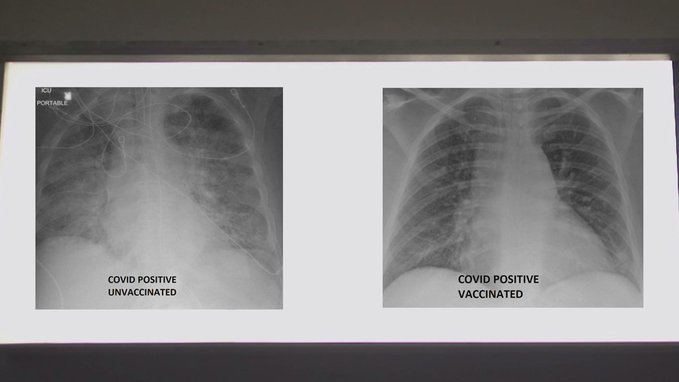

الصور بالأشعة السينية تكشف تأثر التطعيم من عدمه على الرئتين لدى مرضى "كوفيد-19"

شارك طبيب صور الأشعة السينية التي تظهر الفرق بين رئتي شخص تم تطعيمه بالكامل ويصاب بـ "كوفيد-19" وشخص لم يتم تطعيمه.

وعالج الدكتور غسان كامل، مدير وحدة العناية المركزة الطبية في مستشفى SSM Health Saint Louis University في ميسوري، آلاف المصابين بالمرض منذ تفجر الوباء في مارس 2020.

والأشعة السينية لرئتي المريض غير الملقحين بيضاء بالكامل تقريبا، تظهر أنها ممتلئة بالفيروس ولديها ندبات شديدة وهناك نقص في الهواء الذي يدخل الأعضاء.